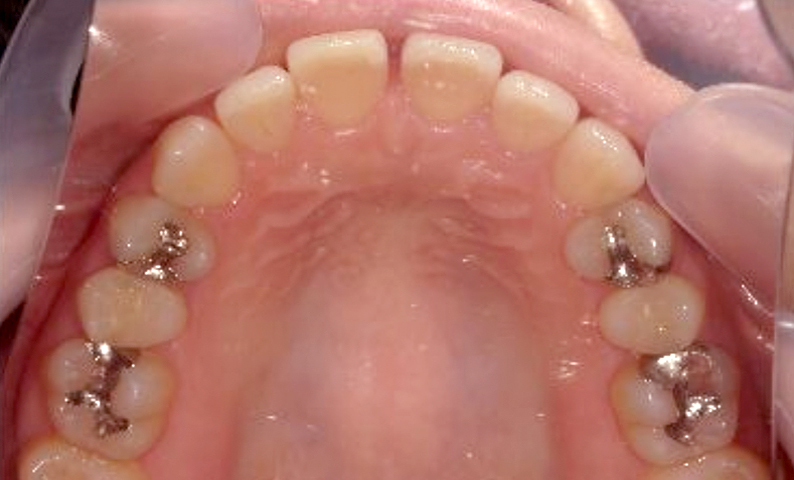

症例_003 上顎だけの部分矯正

治療期間:9ヶ月金額:30万円+税女性前歯のガタガタ八重歯上の前歯だけ

| Before | After |

|---|---|

|